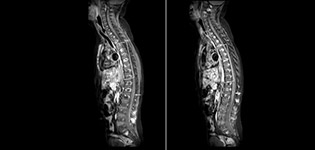

“mDIXON TSE has been one of the most significant improvements in imaging sequences that we have utilized to date at PCH,” says Dr. Miller. “Its multi-parametric acquisition allows us to obtain fat suppressed images and equivalent non-fat suppressed T2 images all in the same sequence. In addition, prior methods of fat suppression could be artifactually corrupted by poor patient anatomy or poor operator application, but with mDIXON we now have a robust and reliable method of fat suppression.”

Fat saturation is historically challenging at the ends of fields of view, especially in total spine imaging and in difficult patient anatomy such as the lower regions of the neck. “Due to the unique fat suppression capabilities of mDIXON, however, these challenges no long apply,” says Dr. Miller. “We routinely obtain homogeneous fat suppression under virtually all conditions. It has also led to some efficiencies by not having to repeat sequences because of that technical failure.”

mDIXON TSE makes a difference

“mDIXON TSE is most useful in patients with lesions or abnormalities in the soft tissues such as the face and neck, and for patients with contrast enhancing abnormalities that are mostly visible with fat suppression,” says Dr. Miller. “All our spine imaging now routinely contains mDIXON water-only T2 images, and this allows us to identify pathology that may be obscured by non-fat suppressed imaging such as injuries of the bone. And it’s not necessary to obtain additional standard TSE T2 images because the in-phase mDIXON images are equivalent to standard TSE T2 images.”

“mDIXON TSE has increased our diagnostic confidence in ruling in or ruling out abnormalities in which fat suppression is critical to diagnosis, such as metastatic disease or osseous abnormalities.”